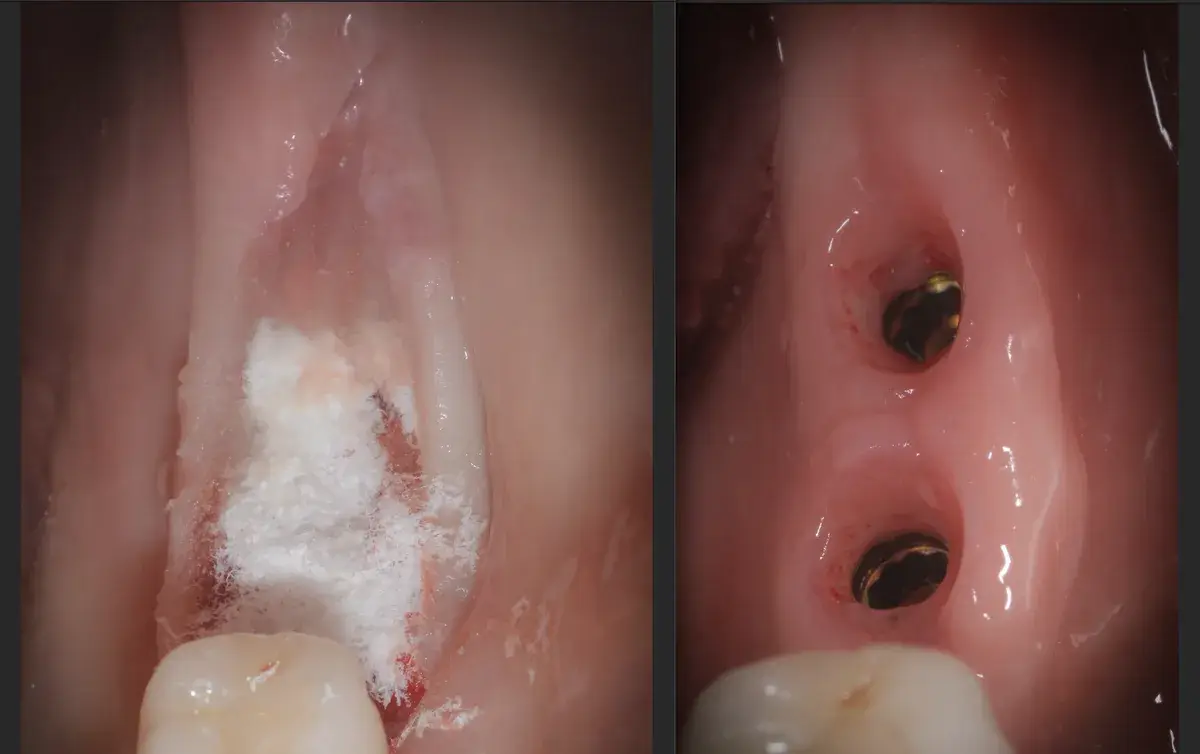

Rappresentazione schematica di un ascesso dentale periapicale e parodontale